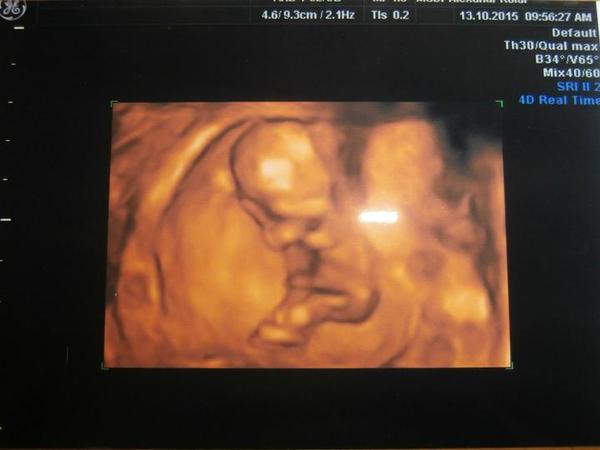

Je to holčička nebo chlapeček? Foto ultrazvuku

@zuziry : na tohle ti rekla holcicku ?? 🙊tak uvidíš třeba ji met budeš. ... já tam vidím výstavního pindika...i s kuličkami,ale jestli ti to řekla tak třeba holčičku mít budeš 😉ten 20 týden je docela přesný pokud jsou nožičky takhle zepředu. A kdyby to byl kluk,tak nevěš hlavu,ja tenkrát i plakala a dnes bych ho nevymenila za nic na světě, mám totiž také 3kluky...😉

@satynka Mně je pohlaví jedno 🙂. No ale jak jsem doma koukala na tu fotku, tak se mi taky zdá že to je kluk. Leda že by to byl kousek bříška, ale to se mi nezdá tak symetrické ( vyznačím to )...

Já tam taky vidím pindíka 😉 .

Tak ještě jak to vidím já 🙂, třeba to i pomůže někomu se lépe orientovat ve vlastních fotkách 😉